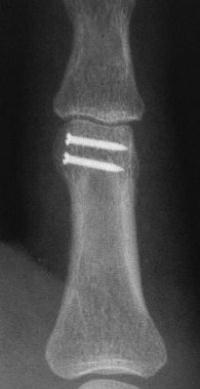

Unicondylar fractures of the phalangeal head are common, frequently unstable and unacceptably displaced. Although some may be treated successfully with percutaneous reduction and fixation, many require open reduction. In these cases, the screws were put right through the collateral ligament and sunk into the cortex. I think the simplest way to do this is to reduce and stabilize with two K wires, then remove the wires and replace with screws, one at a time, so reduction is maintained throughout. 1mm=39/1000" Kwire, so doing the math, here is how you choose the right sized Kwire to use as both drill and provisional fixation:

With two screws, bicortical fixation is not needed. The video below illustrates the steps involved, which are the same with either open or percutaneous fixation.

And another patient.